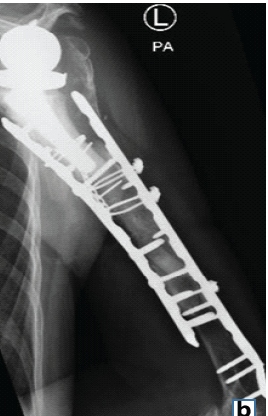

Salvage of Infected Dynamic Hip Screw and Distal Femur Nail Fixation for Ipsilateral Femoral Neck and Femoral Shaft Fracture Using Antibiotic-Coated Custom Long-Stem Austin Moore Prosthesis – A Rare Case Report

Jaideep Das , Nisha Sabat , Ajit S. Rathod , Prathit Kumar , Jyotishman Barman , Sachin S. Sonune ………………………………p.151-155